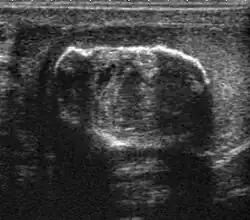

Teratoma Although teratoma is the second most common testicular tumor in children, it affects all age groups. Mature teratoma in children is often benign, but teratoma in adults, regardless of age, should be considered malignant. Teratomas are composed of all three germ cell layers, i.e. endoderm, mesoderm and ectoderm. At ultrasound, teratomas generally form well-circumscribed complex masses. Echogenic foci representing calcification, cartilage, immature bone and fibrosis are commonly seen [Fig. 5]. Cysts are also a common feature and depending on the contents of the cysts i.e. serous, mucoid or keratinous fluid, it may present as anechoic or complex structure [Fig. 6].

Fig. 6. Mature cystic teratoma. (a) Composite Image. Mature cystic teratoma in a 29-year-old man. Longitudinal sonography image of the right testis shows a multilocular cystic mass. (b) Mature cystic teratoma in a 6-year-old boy. Longitudinal sonography of the right testis shows a cystic mass containing calcification with no obvious acoustic shadow.